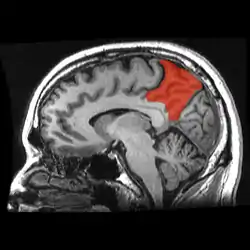

Sagittal MRI slice with the precuneus shown in red. (Anterior to the left.) | |

In neuroanatomy, the precuneus is the portion of the superior parietal lobule on the medial surface of each brain hemisphere. It is located in front of the cuneus (the upper portion of the occipital lobe). The precuneus is bounded in front by the marginal branch of the cingulate sulcus, at the rear by the parieto-occipital sulcus, and underneath by the subparietal sulcus. It is involved with episodic memory, visuospatial processing, reflections upon self, and aspects of consciousness.

The precuneus is located on the inside between the two cerebral hemispheres in the rear region between the somatosensory cortex and forward of the cuneus (which contains the visual cortex). It is above the posterior cingulate. Following Korbinian Brodmann it has traditionally been considered a homogeneous structure and with limited distinction between it and the neighboring posterior cingulate area. Brodmann mapped it as the medial continuation of lateral parietal area 7.